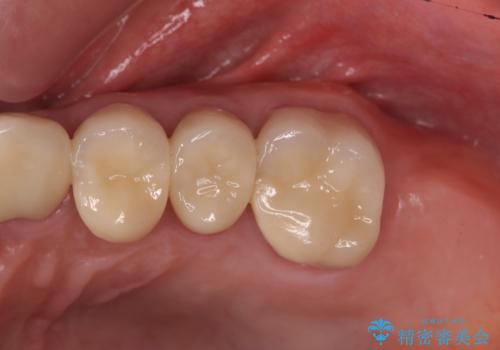

歯ブラシのしやすいクラウンへのやりかえ

クラウンが装着されておらず、つぎはぎだらけの処置歯を、精度の高いセラミッククラウンを用いて歯ブラシのしやすい環境整備を行っていきます。

セラミッククラウンの治療は、天然の歯のような審美性を回復できることも大切ですが、精度が高くきっちりと歯ブラシを行いやすい状態を整えることで虫歯や歯周病の再発リスクを下げることも非常に大切です。